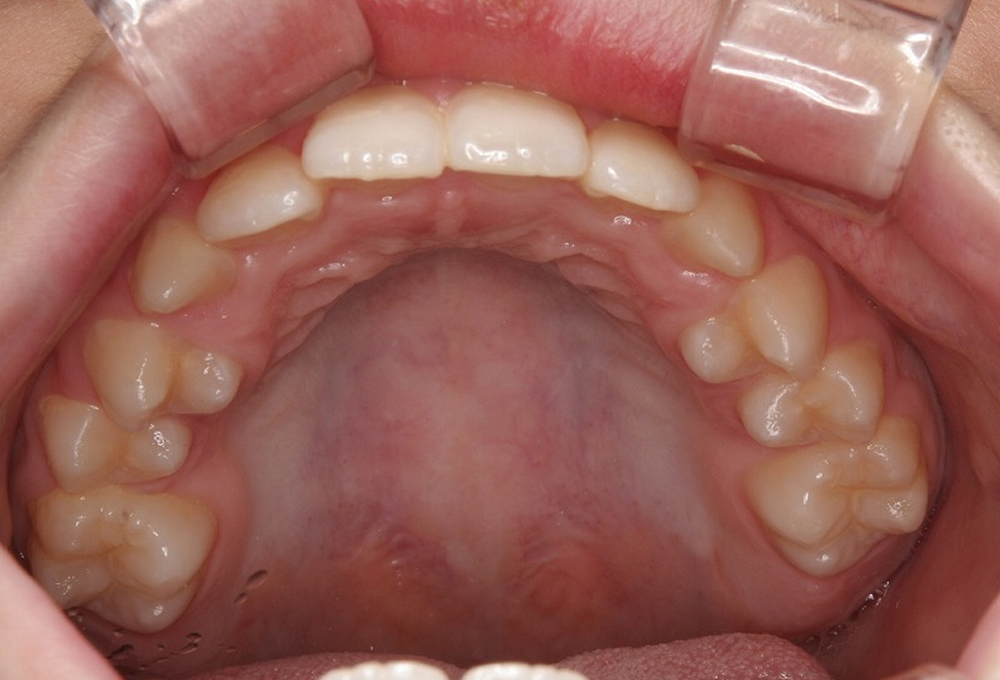

②術前 上顎 叢生